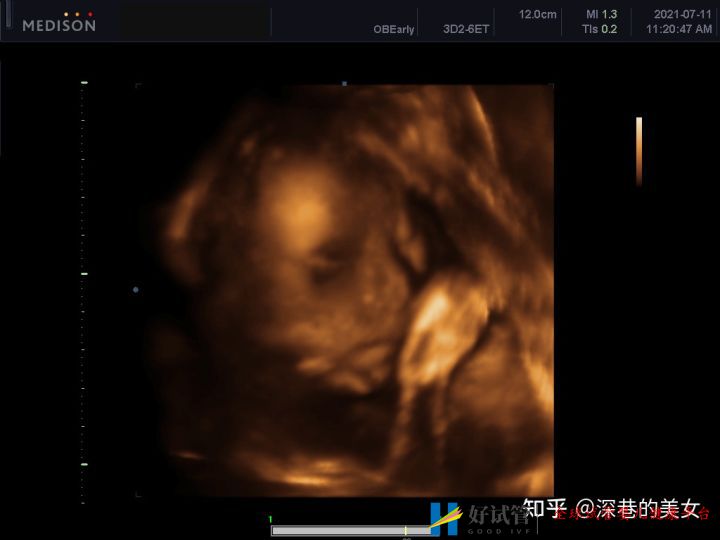

多囊卵巢的促排经历(已怀孕)_好试管网